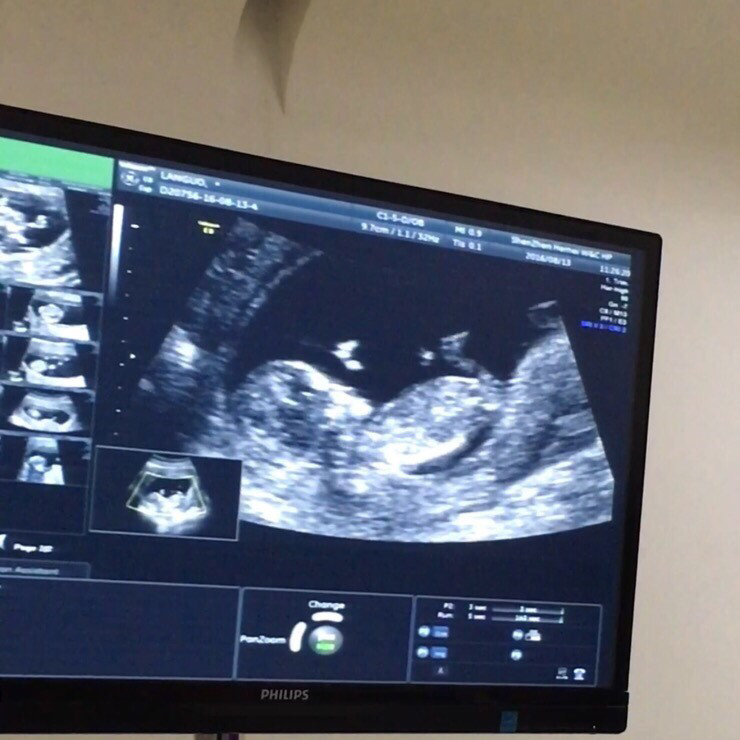

이제 12주 4일이니 만 3개월(12주)을 다 채우고 4개월에 접어든 임신부가 되었다. 안정기로 접어들었다는 사실 하나만으로도 큰 위안이 된다. 그 사이 아가는 어느새 젤리 곰에서 사람이 되어 있었고, 혼자 꼬물꼬물 잘 움직이며 건강히 크고 있었다.

오랜만에 널 보러 가는 길이 어찌나 떨리던지. 건강히 잘 크고 있어주어 고마워. 뭘 아는 듯 꼬물거리며 잘 있다고 보여주어 고마워.

요즘 널 행복이라고 부르고 있어. 뱃속에 있는 시간 그리고 그 이후에도 행복하게 잘 자라길, 너를 기다리며 너의 태명을 부르는 우리 모두 행복하길, 너로 인해 더 행복해질 앞으로를 기대하며 수많은 후보군을 제치고 넌 행복이가 되었단다 :)